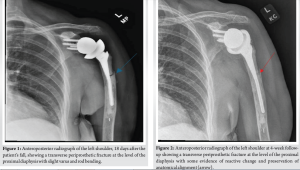

A 77-year-old, otherwise healthy woman presented to the clinic with left shoulder pain after she fell off a small stepping stool at her home and landed directly on her shoulder. Nine years earlier, she had sustained a complex and comminuted proximal humerus fracture, which was treated with open reduction and internal fixation. She subsequently developed a painful greater tuberosity fracture nonunion, which was treated successfully with RTSA with a cemented humeral stem (DJO Encore Reverse Shoulder Prosthesis, Austin, Texas). The patient had no prodromal pain in her arm before the fall, and she self-treated her pain with ice and acetaminophen. Eighteen days after the fall, she presented to the clinic with a complaint of pain in the shoulder with motion, especially while she was getting dressed or rolling over in bed at night. The patient reported no pain at rest in the arm or shoulder, and she had no tingling, numbness, neck pain, or any other injuries related to the fall. Upon physical examination, the patient’s left arm had mild swelling compared to the right but no ecchymosis. There was slight tenderness over her proximal humerus without crepitus or gross motion suggestive of a fracture. There was no tenderness over her joint line, scapula, or clavicle. She was neurovascularly intact with full and equal range of motion in her fingers, wrists, and elbows bilaterally. Radiographs revealed a transverse periprosthetic fracture at the proximal third of the diaphysis, with approximately nine degrees of varus angulation of the humeral component (Fig. 1). Given the stable fracture pattern, intact cement mantle, and minimal symptoms, the decision was made to treat the fracture nonoperatively. The patient was instructed to perform finger, wrist, elbow, and pendulum exercises during the first 3 months. She was prescribed acetaminophen and advised to use ice for pain management. A sling was offered, but she declined because she had had the fracture for several weeks and had only mild discomfort.